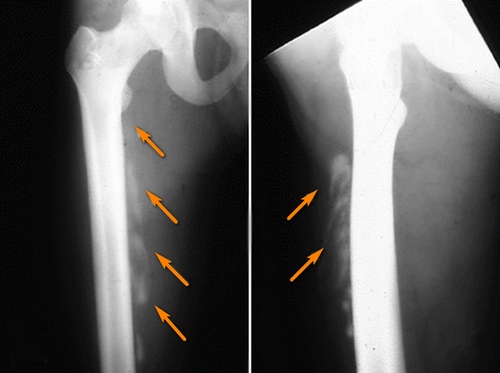

Оссифицирующий миозит. Участки мышц 'окостенели' после ушиба

При трофоневротическом оссифицирующем миозите оссификаты образуются около костей и суставов всего скелета, кроме черепа. Характерны симметричность и множественность окостенений с преимущественной локализацией в проксимальных отделах конечностей. Оссификаты имеют разнообразную форму (пластинчатую, игольчатую, трубчатую, ветвистую, конгломератов, футляров, арок и ) и величину (от нескольких миллиметров до десятков сантиметров). Наиболее крупные из них располагаются вдоль нескольких костей и суставов.

Заболевание может проявляться одной из четырех клинико-рентгенологических форм: периартритической, остеоартропатической, множественного мышечного окостенения и смешанной. Периартритическая форма миозита сходна с болезнью Пеллегрини-Штиды (травматического генеза обызвествление мягких тканей бедра в области внутреннего надмыщелка), но при первой оссификаты более грубы и массивны, созревают дольше, нередко располагаются симметрично, возникают без болевых и вазомоторных реакций и при менее тяжелых повреждениях спинного мозга. Остеоартропатическая форма трофоневротического оссифицирующего миозита сходна с костнодистрофическими процессами при сирингомиелии и спинной сухотке. При этой форме наступают изменения в костях и суставах: кости подвергаются резорбции и иногда ломаются, рядом с переломами образуются оссификаты, которые напоминают либо уродливо гипертрофированную костную мозоль, либо костную опухоль. Форма множественного мышечного окостенения характеризуется множественностью и значительностью размеров оссификатов с тенденцией к генерализации процесса оссификаты могут постепенно несколько увеличиваться. Смешанная форма содержит признаки двух или трех вышеперечисленных форм.